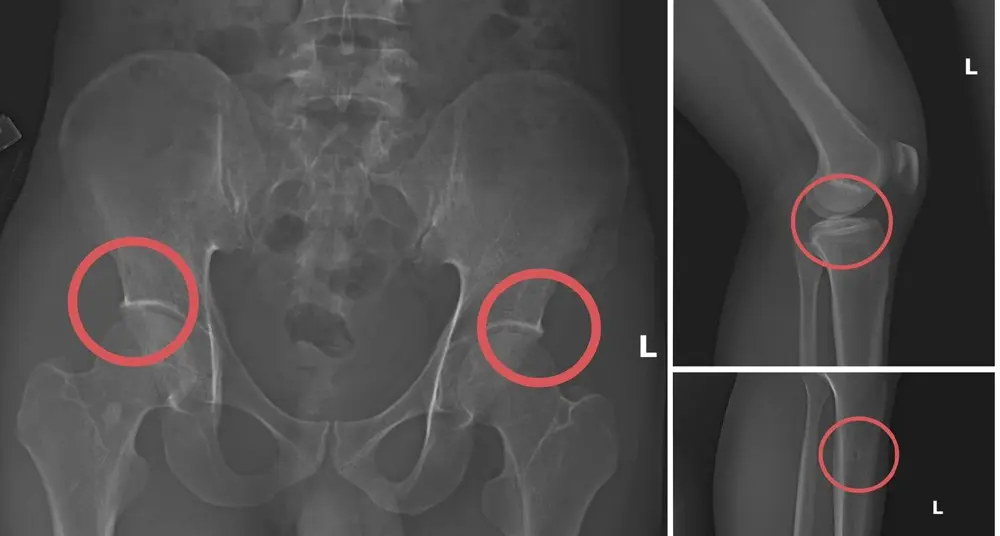

Thủ đoạn của nhóm là tiêm thuốc mê cho các đối tượng mua bảo hiểm sau đó dùng kim tiêm, búa, đinh đục vỡ xương khớp, tạo những thương tích giả nhưng giống hệt các tai nạn thật. Họ cũng dựng các hiện trường giả như tai nạn điện giật, trượt chân ngã suối để hợp thức hóa hồ sơ bệnh án, qua mặt các công ty bảo hiểm và cơ quan điều tra. Những thương tích được tính toán gây tổn thương ở vị trí có mức đền bù cao, khiến việc phát hiện dấu hiệu gian dối rất khó khăn.